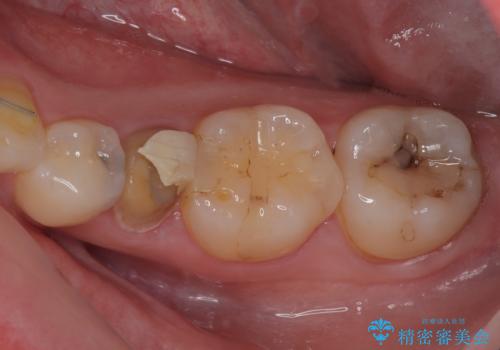

左下が虫歯になっている気がする オールセラミッククラウン

担当医 有澤哲郎